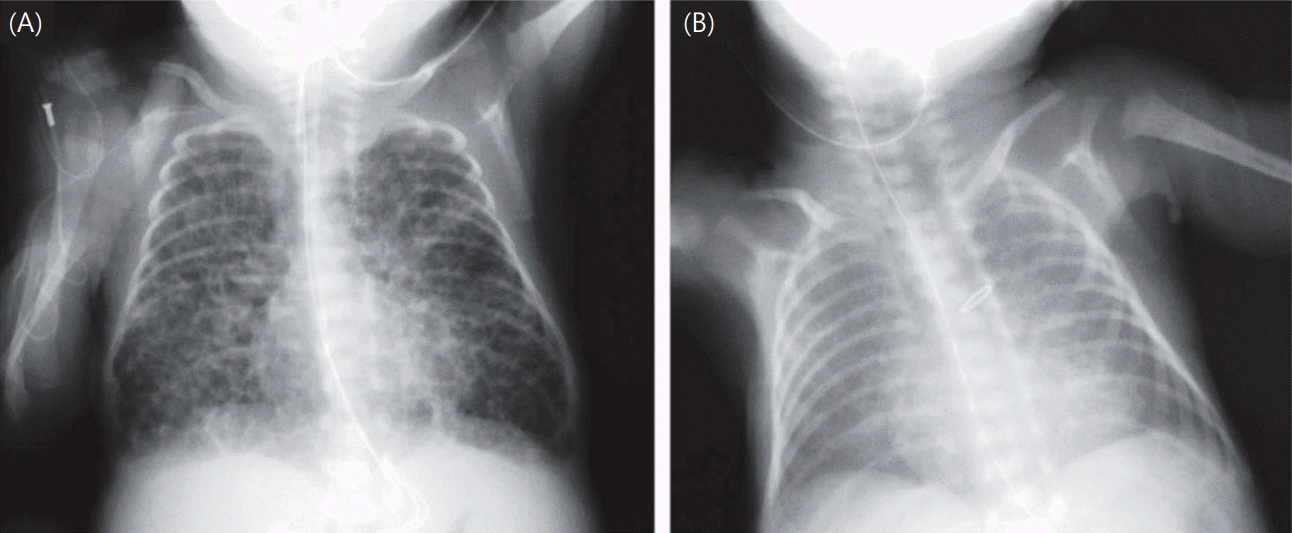

Exposure factors were determined according to the revised Japanese BPD classification. SGA was defined as a BW below the 10th percentile for gestational age according to the Japanese neonatal anthropometric reference curves [15]. These population‑specific values were used because harmonized international birth‑weight z scores were unavailable in the original RCT dataset. Chest radiographs at 28 days were evaluated, and infants judged as having bubbly/cystic changes in the original RCT by participating centers were classified as positive in the present analysis. Representative examples of bubbly/cystic and non‑bubbly chest radiographs are shown in Fig. 1 [16]. In the original RCT, detailed documentation about who interpreted the radiographs and under what conditions were lacking, so the number and specialties of readers and whether the readings were blinded are unknown. Because the images were not available for review, interobserver reproducibility could not be assessed. This limitation reflects real‑world practice in Japan, where neonatologists rather than radiologists typically interpret NICU chest radiographs, and standardized blinded procedures are not routinely used [9]. CAM was defined as acute inflammatory cell infiltration in the amnion, subchorion, or chorion on placental histopathology. RDS was defined as respiratory distress from birth combined with characteristic chest radiographic findings, with surfactant replacement therapy administered as needed. PDA was diagnosed via echocardiography. Data on maternal steroid use and other clinical background variables were extracted from the original RCT database. Potential confounders included BW, GA, sex, 5-minute Apgar score, maternal steroid use, RDS, and PDA. Continuous variables were expressed as mean±standard deviation or median (interquartile range) and compared using the t test or Mann-Whitney U test, depending on normality. Categorical variables were compared using the chi-square test or Fisher exact test. For the primary outcome of severe BPD, univariate and multivariate logistic regression analyses were conducted to calculate odds ratios (ORs) with 95% confidence intervals (CIs). Initially, univariate analyses were conducted to evaluate the association between each candidate variable and severe BPD. Variables with a value of P<0.10 in the univariate analysis or considered clinically relevant (including antenatal corticosteroid exposure) were entered into the multivariate model, alongside classification-related factors (SGA, bubbly/cystic chest x-ray findings, and CAM). A subgroup analysis was also conducted for infants born at <27 weeks’ GA to evaluate the association between BPD subtypes and severe BPD. A 2-sided value of P<0.05 was considered statistically significant. In addition, the predictive performance of the final multivariable logistic regression model was evaluated. Discrimination was assessed using the area under the receiver operating characteristic (ROC) curve, and calibration was examined using the Hosmer-Lemeshow goodness-of-fit test. All statistical analyses were conducted using IBM SPSS Statistics ver. 29.0 (IBM Co., USA).

Bubbly/cystic changes on chest x-ray were identified as the strongest predictor. Chest radiography, which is generally performed in the NICU, provides a surrogate marker of structural injury without additional burden [19]. These radiographic findings reflect parenchymal heterogeneity, hyperinflation, airway obstruction, and microalveolar rupture, all of which have been demonstrated to prolong oxygen and ventilator dependence [16,20]. The identification of this factor as an independent risk indicates the clinical rationale for early intervention strategies based on imaging, such as optimization of lung volume settings, secretion management, and lung-protective ventilation.